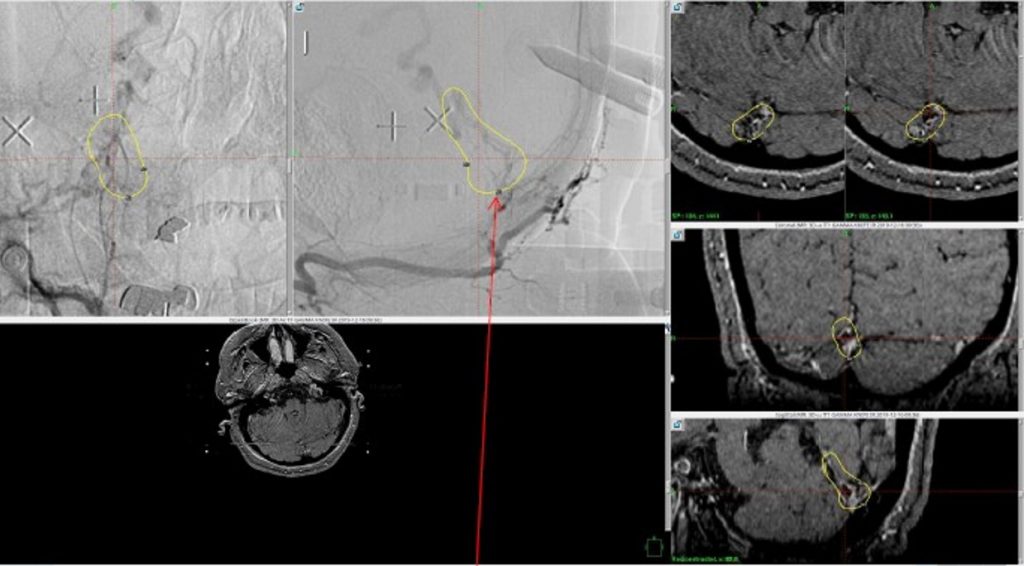

A 55-year-old woman presented with acute onset of severe headache, and possible witnessed seizure. Imaging confirmed intraventricular hemorrhage primarily focused within the fourth ventricle with diffuse subarachnoid hemorrhage within the posterior fossa and along the tentorium as observed on non-contrast CT and MRI of the Brain (Figure 1).

Figure 1. A and B) Non-Contrast CT Axial and Coronal demonstrate large, ruptured Varix/Aneurysm along the Incisura of the posterior fossa which appears to have mixed hemorrhagic components and enhancement on MRI T2 and post contrast imaging (C and D).